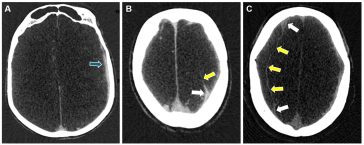

Revolutionizing Chronic Subdural Hematoma Care Through Advanced Diagnostics and Treatment

Chronic Subdural Hematoma: A Shifting Landscape in Neurosurgical Care The management of chronic subdural hematoma (CSDH) has been a topic of heated discussion in the healthcare community for many years. With an annual incidence that ranges from 1.7 to 20.6 per 100,000 people—and climbing due to an aging global population and increasing use of anticoagulant […] More